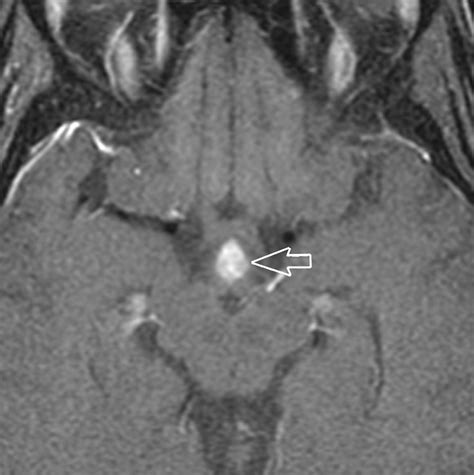

• Imaging studies: Magnetic resonance imaging (MRI) is the gold standard for visualizing the pituitary gland and the infundibular stalk. It can detect tumors, inflammation, and other structural abnormalities.

• thickening of the pituitary stalk

• causes of pituitary stalk thickening